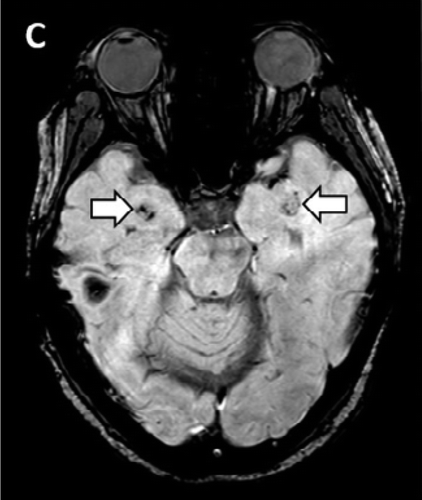

新型コロナウイルスの感染が全世界中で広がるなか、肺炎症状だけでなく、味覚や嗅覚などの異常も報告されるようになったが、米国の研究で、脳の一部で炎症や壊死が進行する「急性壊死性脳炎」を発症していたことが明らかになった。

米ミシガン州デトロイトのヘンリー・フォード・ヘルスシステムの神経科医エリッサ・フォーリー博士らの医療チームが放射線医学誌『ラジオロジー(Radiology)』に先月31日付で発表した症例報告によると、航空会社に勤務する58歳の女性は先月19日、パニック障害や方向感覚の欠如、意識不明などの状態で同病院に救急搬送された。

同時に、頭部のCTスキャン検査を実施したところ、脳の中心部分にあって、視覚や聴覚、運動などをつかさどる「視床」に損傷が見つかり、壊死が起きているのが判明。さらに脳のMRI検査の結果、側頭葉の血管が破裂して出血しているのも見つかった。

当初、急性脳炎を疑っていた医療チームは、免疫機能が暴走して、自身の体にダメージを与える「サイトカインストーム」を起こしていると判断。サイトカインとは、白血球など免疫系の細胞から分泌されるタンパク質で、ウイルスや病原体の増殖を抑えるなどといった役目を果たす。サイトカインストームとは

しかし、免疫系のバランスが乱れて、サイトカインの制御ができなくなると、サイトカインストームといってサイトカインの過剰分泌を起こし、ひどい場合は死に至ることもあるという。

ヘンリー・フォード・ヘルスシステムのチームは「新型コロナウイルスが原因で、急性壊死性出血性脳症を起こした初めての症例だ」として、現場で働く臨床医や放射線医は、この症状の進行に注意するよう呼びかけている。